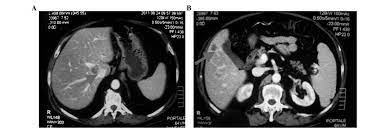

Clinical Characteristics And Prognostic Factors Of Prostate Cancer With Liver Metastases Semantic Scholar

Clinical Characteristics And Prognostic Factors Of Prostate Cancer With Liver Metastases Semantic Scholar from d3i71xaburhd42.cloudfront.net